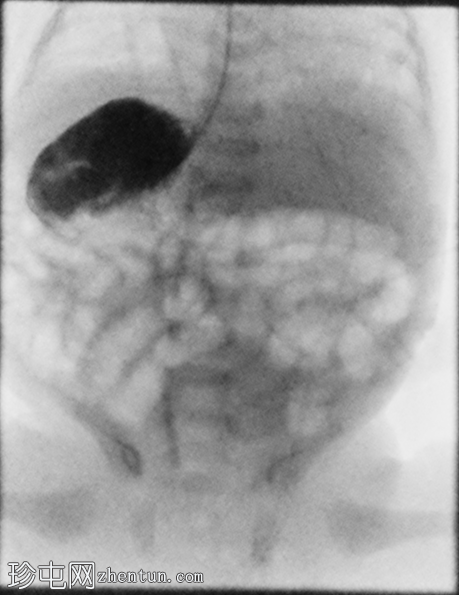

侧位

胃位于右上腹。观察到轻度中段食管反流。造影剂在近端十二指肠的延迟通过量极少,这属于异常情况。

延迟正位和侧位X线片显示肠内容物通过时间极短。